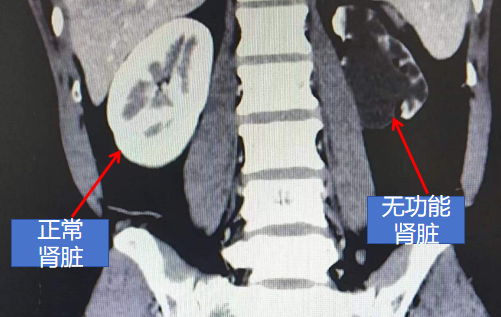

33岁的王女士,近两个月来因左侧腰痛并伴有活动后肉眼血尿而就医。经检查,被诊断为左肾完全性鹿角型肾结石,这种结石充满整个肾脏,直径达5厘米,且肾脏几乎没有积水,治疗难度较大。

针对王女士的病情,陈雪松医生制定了两步法微创治疗方案。首先,通过经皮肾镜碎石术快速击碎并取出大块主体结石;随后,利用经尿道输尿管软镜对肾脏内残留的小结石进行“清扫”。

这一方案既快速又有效,避免了多次穿刺带来的损伤。

经过两次手术及后续治疗,王女士的肾结石被完全清除。她对微创手术的效果非常满意,认为这一治疗方式既安全又有效。